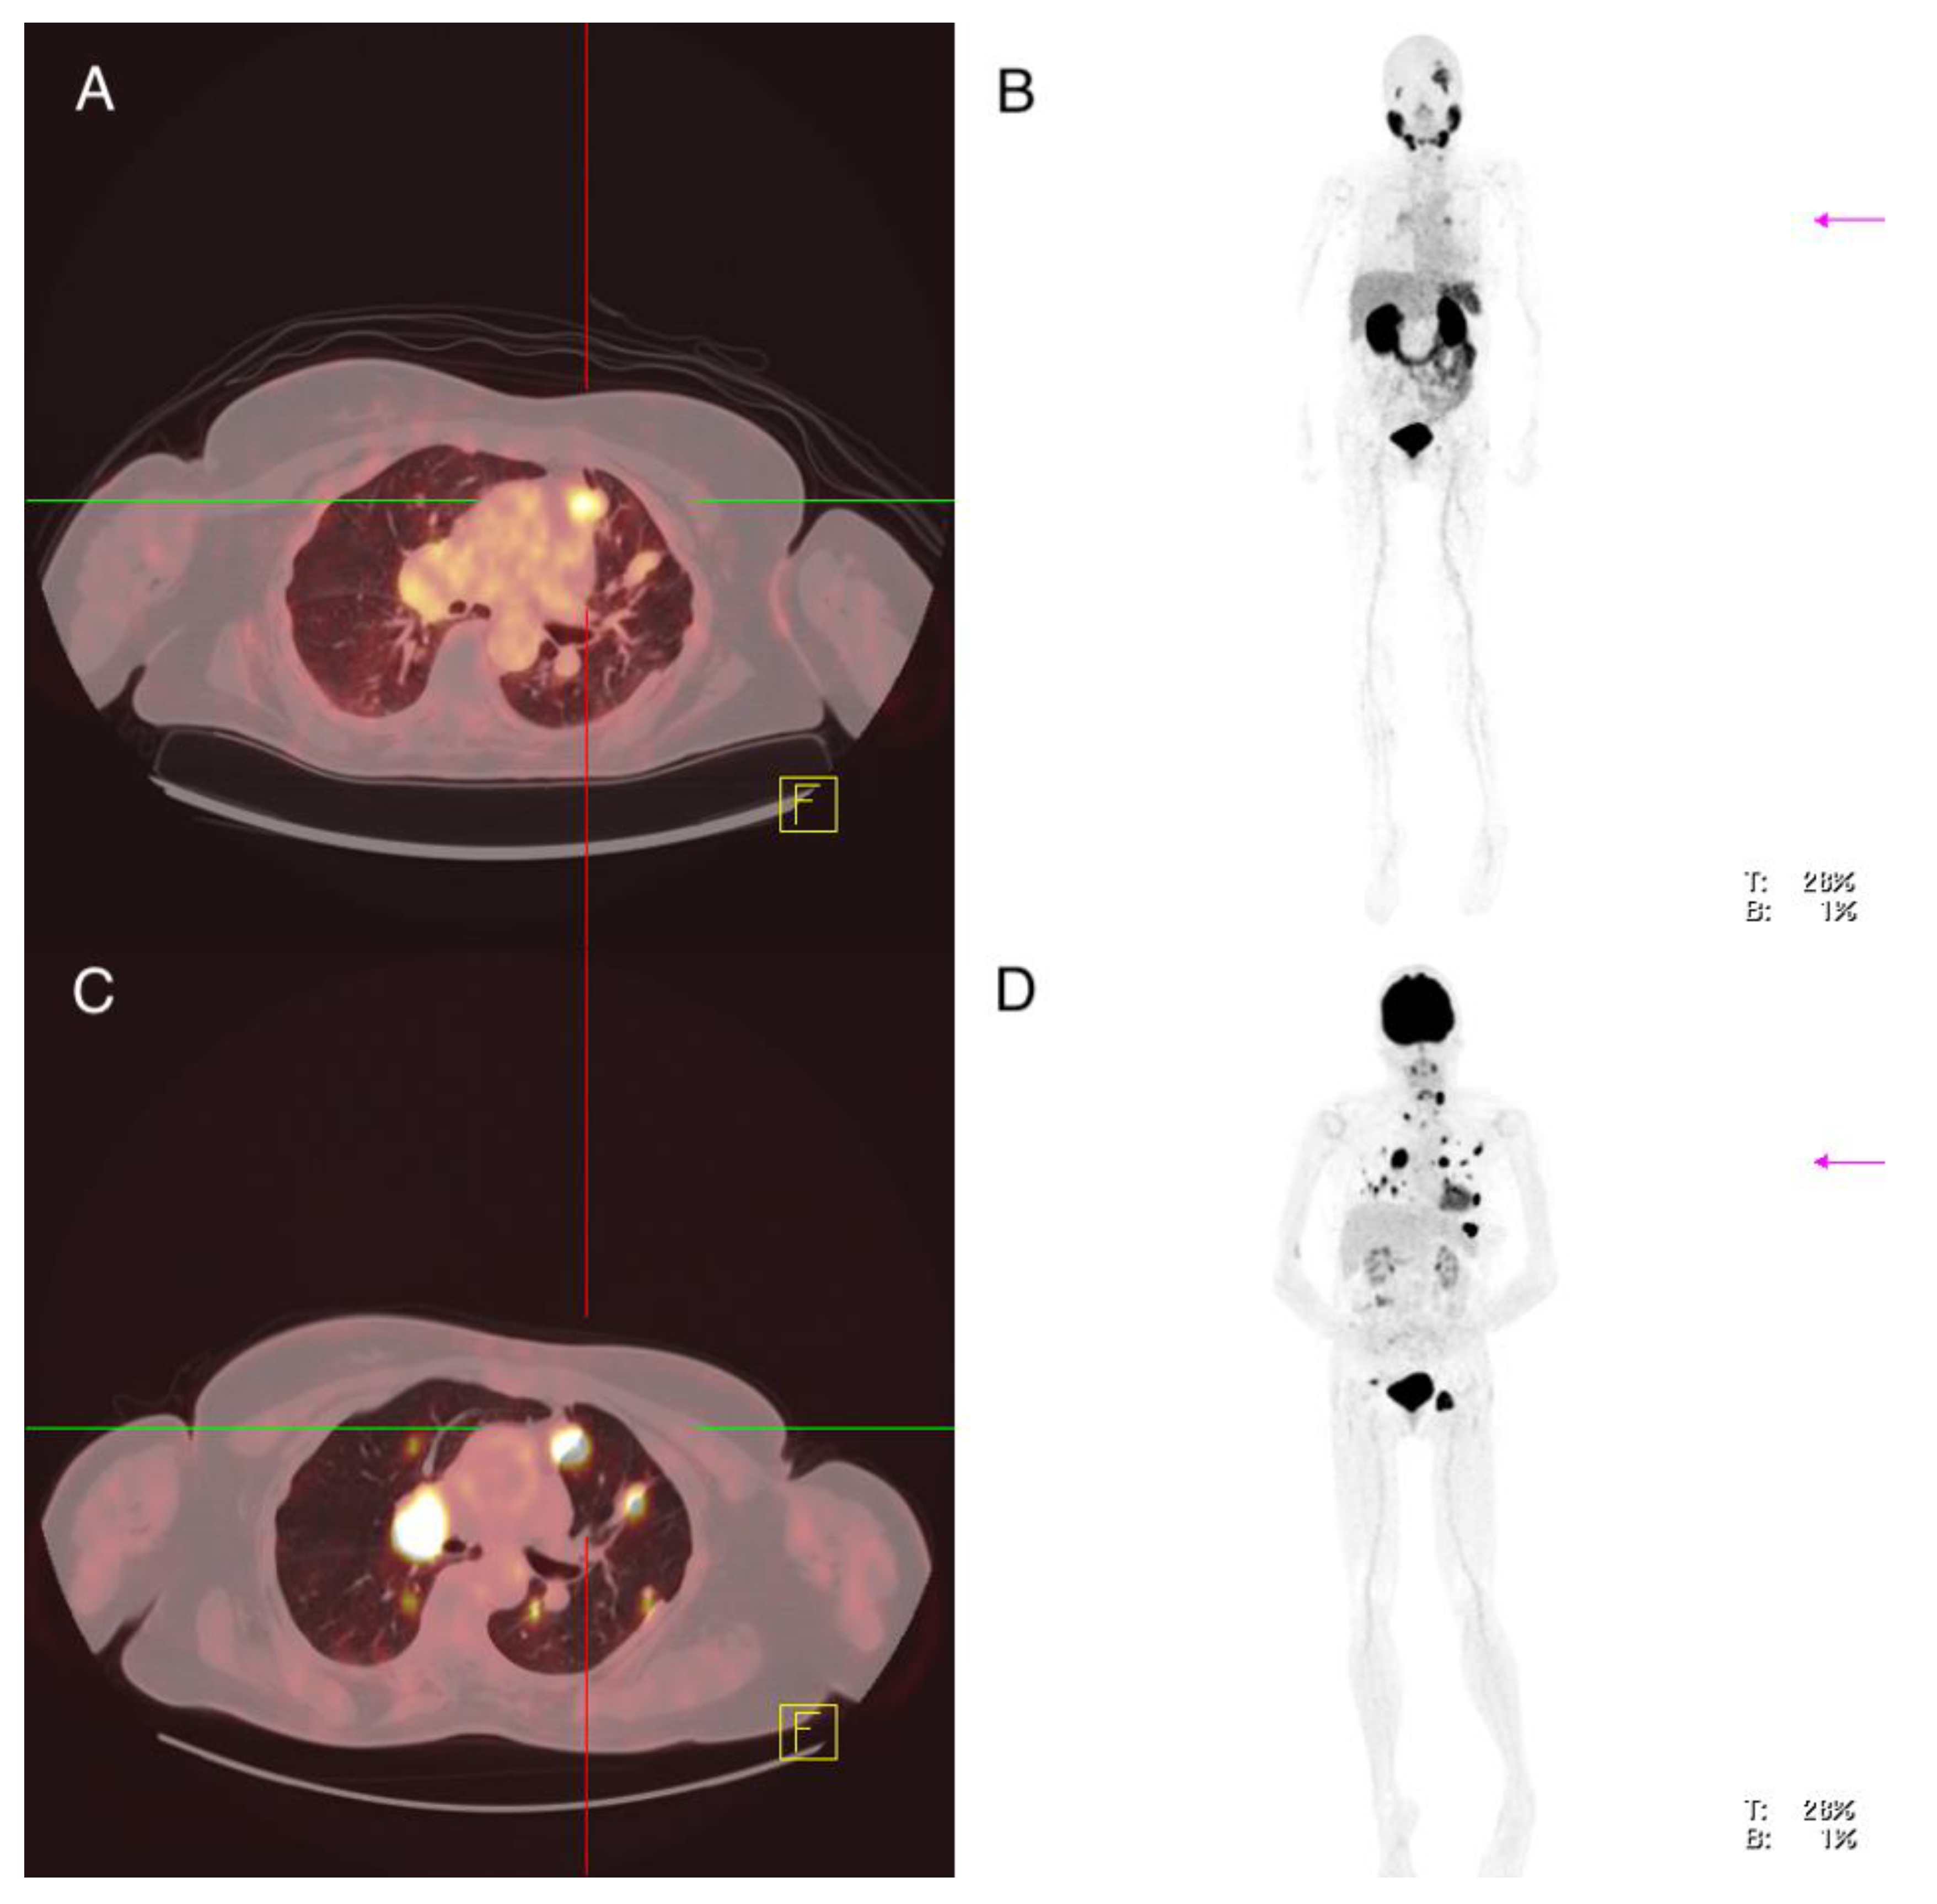

3.3.1. Setting No. 1—18F-FDG-PET/CT Positive, 68Ga-PSMA-PET/CT Negative

Patient 1: Male, ATC, 59 Years Old at the Time of Diagnosis

Patient 7: Female, PDTC, 61 Years Old at the Time of Diagnosis

| 1 | 2020 | PSMA: 2020 FDG: 2020 | 1 | TB 1 (local recurrence) (n = 1) 1.9 | 16.3 | 2.5 | Primary tumor Soft tissue surrounding thyroid gland | Strong expression Strong expression |

| LN2 (mediastinal) (n = 1) 2.2 | 2.7 | 3.3 | ||||||

| PM 3 (n = 7) 0.7 (0.3–1.2) | 2.7 (1.5–7.9) | 1.3 (0.6–2.6) | ||||||

| 2 | 2020 | PSMA: 2020 FDG: 2020 | 1 | PM 3 (n = 2) 2.1; 2.2 | 21.2 (14.1; 28.3) | 3.25 (4.0; 2.5) | Primary tumor Pulmonary metastasis | Strong expression Strong expression |

| 3 | 2007 | PSMA: 2017 FDG: 2016 | 83 | PM 3 (n > 10) 1.0 (0.5–1.1) | 12.6 (6.6–25.3) | 3.4 (2.0–4.3) | Primary tumor Lymph node metastasis (cervical) Pulmonary metastasis | Low expression Low expression Low expression |

| 6 | 2010 | PSMA: 2017 FDG: 2017 | 171 | TB1 (tumor recurrence) (n = 1) 10.7 | 67.9 | 4.2 | Tumor recurrence Lymph node metastasis (cervical) | Low expression Low expression |

| LN 2 cervical (n = 1) 1.9 mediastinal (n = 1) 6.7 | 48.4 55.9 | 4.1 5.7 | ||||||

| PM 3 (n > 10) 1.9 (1.6–3.6) | 35.4 (29.4–51.5) | 3.8 (2.5–6.3) | ||||||